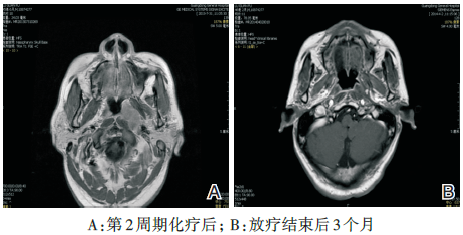

鼻咽+颈部MRI(2013-07-31)示:(1) 鼻咽左侧壁可见一椭圆形软组织肿块影, 最大径约31 mm× 19 mm, 肿块累及头长肌、腭帆提肌、腭帆张肌、翼突。左侧咽隐窝及咽鼓管咽口变窄、消失, 右侧咽隐窝及咽鼓管清晰。双侧颈部Ⅱ 、Ⅲ 区见多发小淋巴结, 最大者约8 mm× 10 mm。诊断:鼻咽左侧壁肿块, 考虑鼻咽癌并累及头长肌、腭帆提肌、腭帆张肌、翼突(见图1)。

图1 鼻咽颈部MRI图像(2013-07-31)